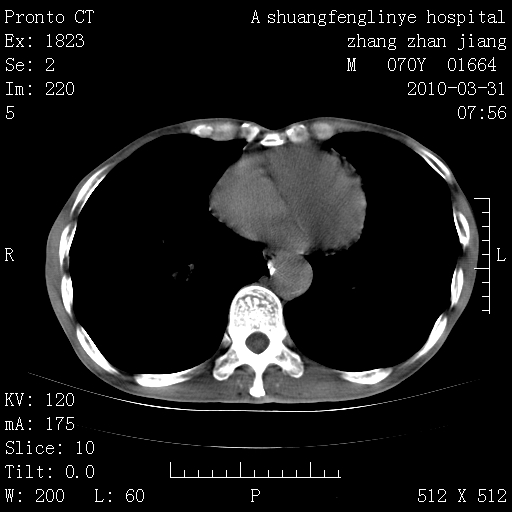

标题: CT25450:肺结核?

双上肺继发型tb并左上空洞形成,主动脉冠脉钙化。

1)两肺上叶继发性肺结核并左肺上叶空洞形成。2)冠状动脉及主动脉钙化。